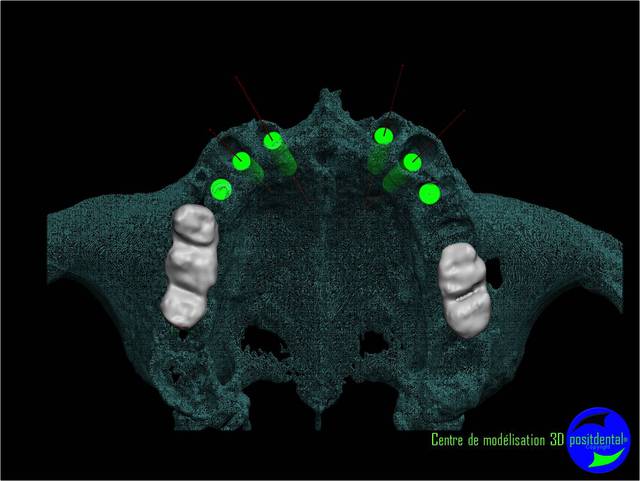

La vidéo présente à partir des plans de traitements, des chirurgies de beotien , des dispositifs médicaux sur mesure positdental et positguide la mise en charge immédiate post-extractionnelle d’un bridge provisoire à armature métal en prothèse fixe sur implants cône morse donc sans vis de maintien. Une question est émise « comment obtient-on ce résultat ? ». Une partie des réponses comme la prédictibilité, la reproductibilité peuvent y être déduite pour d’autre il faudra la bonté de beotien de faire partager les résultats clinique.il nous fait la générosité de poster la phase cicatriciel à 7 jours et des photos de la chirurgie sur un cas.

planif cas 1

Si tu as suivi les cas présentés depuis plusieurs années les bridges provisoires ont une armature métal pour la rigidité du fixateur externe, l’intervention se déroule en 1 seul temps chirurgical donc sans prise d’empreinte, c’est pour cela que je parle de MCI. Pour la passivité du bridge avec le système Nobel Guide et leurs piliers expansifs je n’ai vue aucun cas clinique présenté sur le forum. As-tu déjà utilisé le procédé ? Dans les cas présentés sur la vidéo, aucune clé de positionnement n’a été utilisée, le placement des piliers se fait selon la simulation implantaire assistée par ordinateur, leurs présentations a été faite en prospective par OTP, modèle 3D et à la demande de beotien la solution pilier fixe a été retenu à la place du bridge transvisé. Quel sont les compléments d’information que tu as besoin et ou la photo ne te suffi pas ? Pour le protocole d’une MCI, empreintes des maxillaires, dimension verticale de l’occlusion, définition de l’esthétique souhaitée, prescriptions, réalisation du Positscan, traitement des informations à partir des données DICOM, simulation implantaire assistée par ordinateur, validation, réception des DMSM selon les types d’implants et encastillages les procédures varient. Quel système implantaire utilise-tu ?